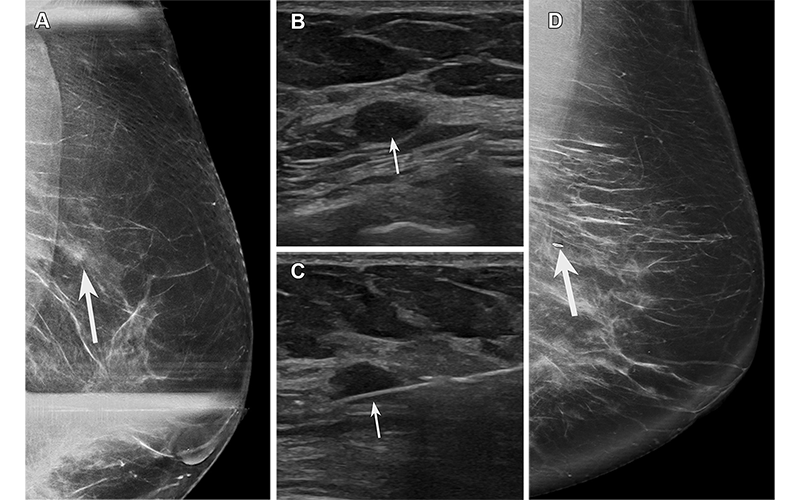

FEA found at biopsy of a hypoechoic mass in a 64-year-old asymptomatic woman recalled from screening mammography. (A) Spot compression exaggerated craniocaudal lateral (XCCL) mammogram of the left breast shows an asymmetry (arrow) in the outer breast at a posterior depth. (B) US image of the left breast shows a corresponding irregular hypoechoic mass (arrow). (C) Image from US-guided biopsy shows a needle (arrow) traversing the mass. (D) Postprocedure XCCL mammogram of the left breast shows a marking clip (arrow) in the expected position. Pathologic analysis yielded FEA on a background of proliferative fibrocystic changes, considered elevated risk and possibly discordant due to the presence of a mass. The patient went on to surgical excision, which yielded FEA and fibroadenoma. The fibroadenoma accounts for the mass at imaging and was likely undersampled at core biopsy. https://pubs.rsna.org/doi/10.1148/rg.230016 © RSNA 2023